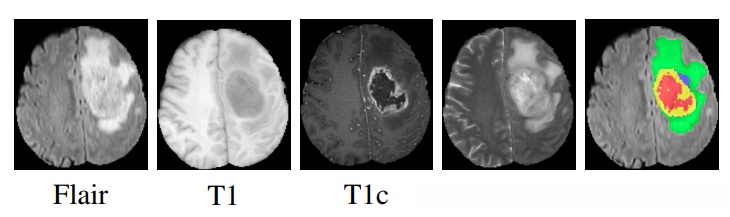

上图展示了四种MRI模态下HG gliomas患者的脑肿瘤图像(绿色为水肿区域),最后一个图是由专家绘制的肿瘤边界轮廓(红为坏死区、黄为增强区、蓝为非增强区)。